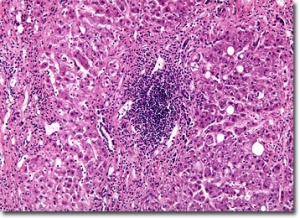

От 9 март 2011 г. (сряда) до края на юни 2011 г. в София ще функционира кабинет за анонимно и безплатно изследване за хепатит В и С. Дейността на кабинета е продължение на миналогодишната Национална кампания за анонимно и безплатно изследване за хепатит В и С.

Изследванията ще се извършват всеки делничен ден от 8:00 до 18:00 ч. на адрес ул. „Георги Софийски“ № 3, поликлиника ВМА, ет. 2, кабинет 201 (Лаборатория „Имунолаб“). Всички желаещи могат да се изследват без предварително записване, чрез бързи скринингови тестове с венозна кръв, като при положителен скринингов резултат ще се извършва допълнителен анализ чрез ELISA. Всички пациенти, носители на вируса на хепатит, ще бъдат насочвани за по-задълбочени изследвания и лечение.